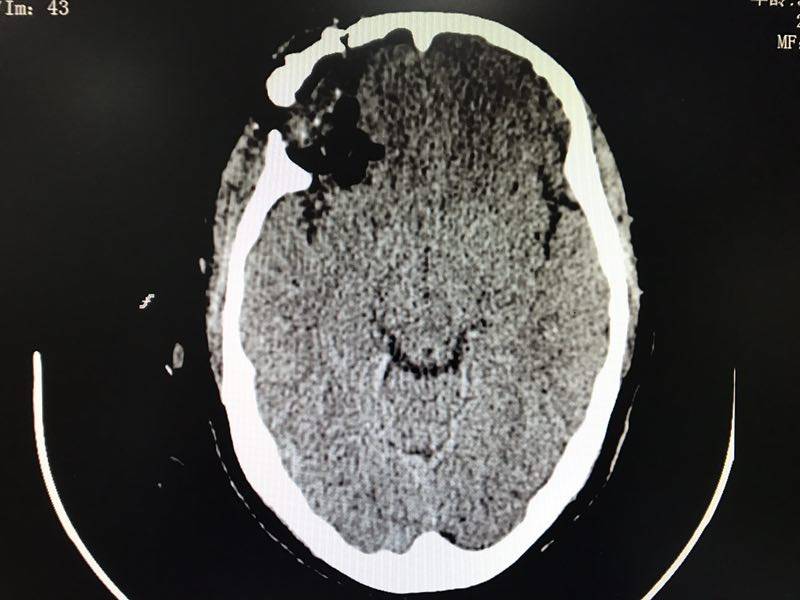

當(dāng)時(shí),它住在一位52歲阿姨的腦子里,本來(lái)和平共處,相安無(wú)事。有一天不小心喝多了吃撐了,一下子胖了不少,將正常的腦組織擠了一下,阿姨頓時(shí)就抗議了,暈得天旋地轉(zhuǎn),嘔吐不止,還觸發(fā)了她的冠心病,出現(xiàn)了胸悶、心悸的癥狀。正當(dāng)腦膜瘤為自己的“蝴蝶效應(yīng)”洋洋得意時(shí),阿姨被送到了惠州市第三人民醫(yī)院神經(jīng)外科,一個(gè)頭顱CT便初步將它鎖定。

術(shù)前三維血管重建

以上為術(shù)前腦膜瘤不同切面pose照(冠狀位、矢狀位、軸位)